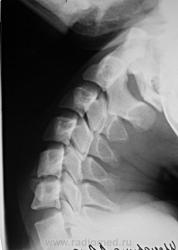

Дело в том, что именнов этом ПДС, определяется фиксация и ограничение объёма движений. Как видите - ни при згибании, ни при разгибании ширина и форма межпозвонкового диска не изменяется. Да и форма тела С5 мне кажется весьма отличной от других тел... Такое впечвтление, что сформирован неоартроз.

Там действительно есть неоартроз с деф артрозом, но  это точно не сами позвонки, а части избыточно развитых отростков...

Спасибо Анатолий Иванович, понял что это гиперплазированные поперечные отростки тел С5 и С6, с сформированым между ними неартрозом и деф. артрозом. Вообще эта пациентка какаято странная - жалуется на похудение одной (правой) половины тела. Напрвляли её на ПКОП - ничего кроме сколиоза, с небольшим торсионным компонентом нет. Тут вот шейный отдел, надо бы грудной снять, а тут опять кто то из врачей сказал, что много уже рентгена и на грудной не направили...